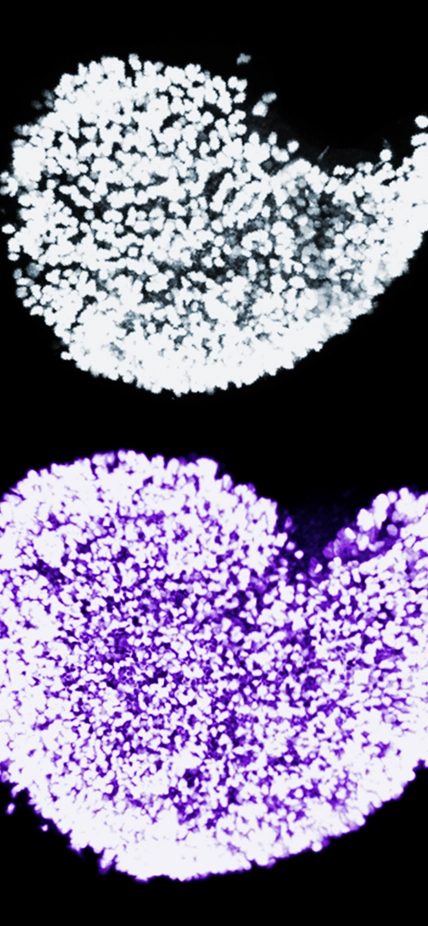

This image displays the dramatic increase in the endowment of immature egg cells in newborn mice when Fetal Oocyte Attrition is prevented from occurring. Shown in white is an ovary exposed to normal physiological activity of the jumping gene LINE-1. Shown in purple is an ovary that's been treated with AZT to inhibit LINE-1 and mutated to turn off the DNA damage checkpoint Chk2. The nuclei of individual immature egg cells are labeled by a germ cell-specific marker. Photograph is courtesy of Marla Tharp.

Taking this idea to the next stage, the research team expanded their investigations by using AZT in mice lacking a protein called Chk2, which detects DNA damage and either repairs it or flags the cells where this genetic material is housed for death. When the LINE-1 jumping gene was inhibited by AZT, and the Chk2 protein was rendered ineffective by mutation, the reserve of egg cells increased.